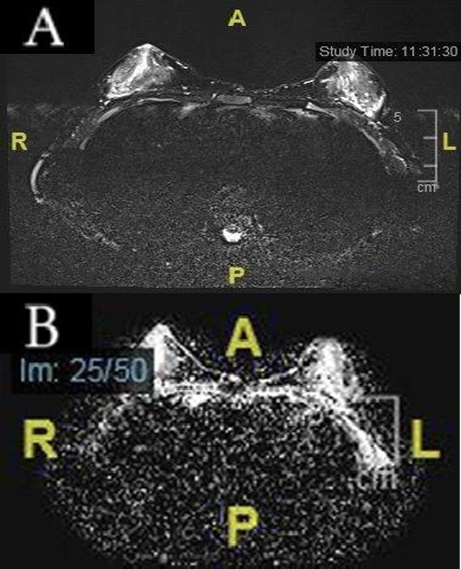

Patient was admitted for further investigation under the care of Pediatric Surgery. MRI Breast with Contrast was done and was unremarkable. A sample for Cytology from nipple discharge showed negative results.

Fig. 1 A) Axial T2-weighted breast MRI shows appearance of the patient’s breast. B) ADC normalization of both breasts is seen.